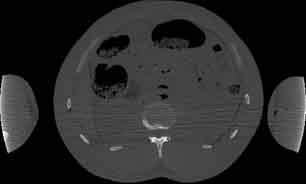

Visible Human male: Sectio transversalis 1615

CT

NMR

Pd                          / T2 \                         T1